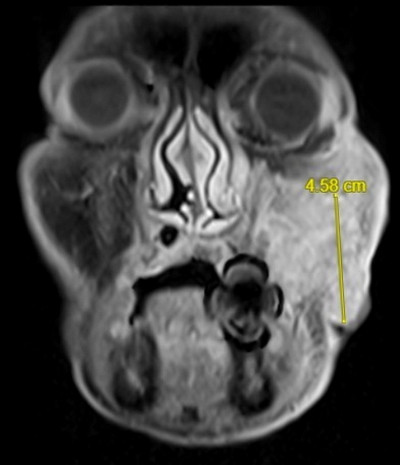

台北慈濟醫院血液科主任高偉堯指出,白血病又稱血癌,骨髓是人體的造血器官,骨髓癌變會過度增生不成熟的白血球,影響人體血液功能,侵犯其他器官,也就是「急性骨髓性白血病」,症狀通常以感染、發燒、出血、貧血為主,可能與基因異常有關,先期檢查可藉由白血球數量、基因變化狀態等判斷預後狀況,決定病人是否需要移植骨髓。